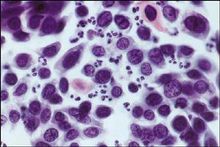

感染後腎小球腎炎2.電鏡腎活檢可見50%以上的系膜區有電子緻密物沉積,成分尚不清楚,可能包含IgM成分。在一些患者中可發現內皮下電子緻密物,但很少發現毛細血管壁內有電子緻密物。上皮細胞足突可呈瀰漫性腫脹或消失,偶見胞質破碎。常見輕微的基底膜改變,如基底膜增厚或不規則。